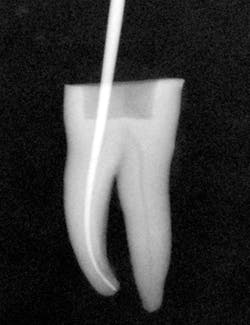

I then use the Tango finishing instrument (double blue band on the latch head) in the same manner as described above. Always use the instrument wet. If you cannot achieve length, repeat the use of the Tango shaping instrument or use a 30/.04 SafeSider instrument to go to measurement. Confirm the Tango finishing instrument reaches the apical measurement. Move the instrument continuously against the canal walls until there is no resistance. I then fit the Tango-Endo gutta-percha point (figure 3). Figures 4 and 5 demonstrate the pre- and postop clinical radiograph.

Figures 4 and 5: Clinical pre- and postoperative radiographs using the Tango techniques described.

The result is a final shape that reflects the original canal anatomy without excessive mesiodistal tooth structure removal and inadequate removal of buccolingual tooth structure.